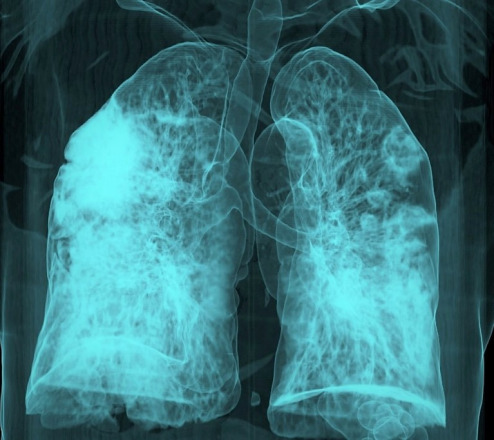

In the years since the COVID-19 pandemic began, scientists have worked to understand its long-term consequences. Now, a new international study reveals a concerning possibility: the virus’s spike protein may actively contribute to the development of lung cancer.

Clinicians have long observed that many COVID-19 survivors develop interstitial lung fibrosis, a condition marked by scarring of lung tissue and known to increase cancer risk. Until now, however, the mechanism connecting viral infection to tumor development has remained unclear.